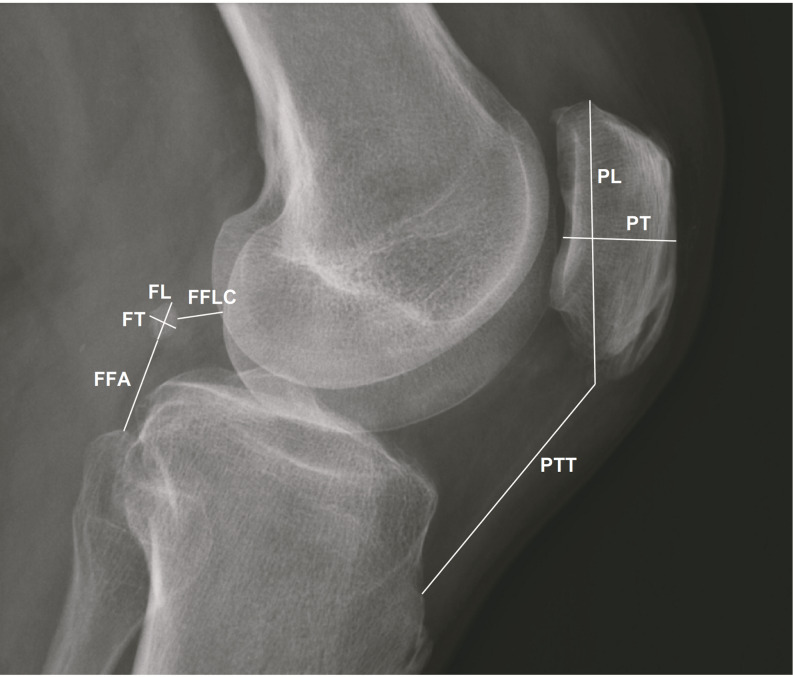

Purpose: The fabella is a sesamoid bone located posterior to the lateral femoral epicondyle within the gastrocnemius muscle. While commonly present in mammals, its prevalence in humans remains unclear, with reported rates ranging from 3 to 87%. Fabella is more frequently observed in Asian and Australian populations but is rare in European and American populations. Although often asymptomatic, it can sometimes cause knee pain, known as "fabella syndrome," and may contribute to neurological symptoms when in proximity to the common fibular nerve. Given the limited awareness of fabella's presence, this study aims to assess its prevalence and anatomical characteristics to aid in the differential diagnosis of knee pain.

Methods: A retrospective analysis was conducted on 500 knee radiographs from 383 patients experiencing knee pain. Data collected included patient age and sex, fabella presence and dimensions, fabella location (distances to surrounding bony structures), patella dimensions, and patellotibial ligament length.

Results: Fabella was detected in 31 females (14.76%) and 29 males (25.66%). Among the examined knees, fabella was present in 40 (12.82%) of female and 39 (20.74%) of male knees. The mean fabella length was 8.85 mm (SD = 2.59), and thickness was 5.63 mm (SD = 1.88), with no significant sex differences. No correlation was found between fabella size and patella dimensions. Notably, patients with fabella were older on average, and bilateral fabellae were significantly larger than unilateral cases (p < 0.05).

Conclusion: Fabella is a relatively common anatomical variant in Central European populations, present in one in six women and one in four men. Its increased prevalence in older individuals suggests a potential age-related development. A comprehensive understanding of fabella anatomy may aid clinicians in diagnosing and managing unexplained knee pain, particularly in elderly patients.